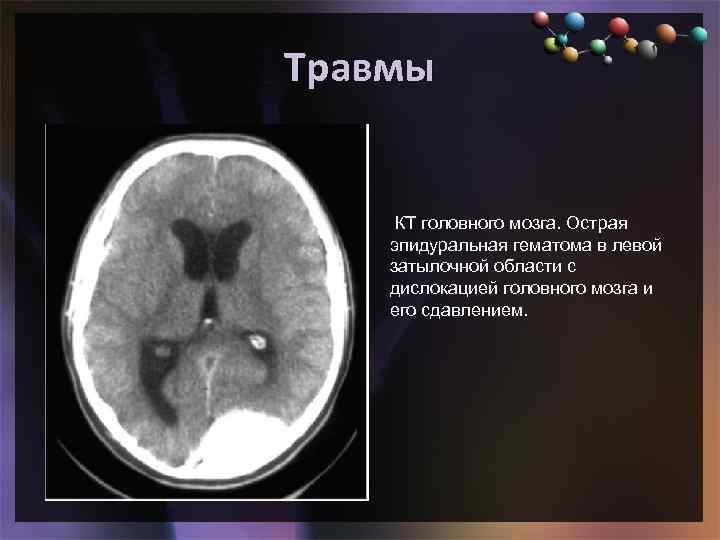

Травмы • Подзаголовок слайда КТ головного мозга. Острая эпидуральная гематома в левой затылочной области с дислокацией головного мозга и его сдавлением.

Травмы • Подзаголовок слайда КТ головного мозга. Острая эпидуральная гематома в левой затылочной области с дислокацией головного мозга и его сдавлением.